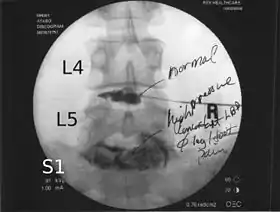

![]() Lumbar provocative discography showing a degenerated disc, L5-S1 with normal disc L4-L5 | |

Spinal MRI is the imaging of choice to investigate the spine and intervertebral discs.[1] Meanwhile, lumbar discography is used to demonstrate degeneration and herniation of lumbar intervertebral discs by injecting a dye into the nucleus pulposus of the discs. The procedure is also used to reproduce pain back pain for those who have such symptoms. Lumbar discography is also used to access the response of a subject to anaesthetic injection. Other uses include suspected discogenic pain without radicular sign (pain travelling to lower limbs along a dermatome) and confirmation of normal intervertebral discs above and below a site before spinal fusion.[1] However, evidence supporting the usefulness of lumbar discography in recognizing intervertebral disc problems is limited.[1] There is no role for cervical or thoracic discography in diagnosing disc pathologies at the cervical or thoracic regions.[1][2]

Non-ionic contrast media such as iopamidol and iohexol are used.[1] Needles are inserted through the back into the disc near the suspect area, guided by fluoroscopic imaging. Fluid is then injected to pressurize the disc, and any pain responses are recorded.

A contrast agent is introduced, and after the procedure, a CT scan identifies leakage from the discs to identify any spinal disc herniation.